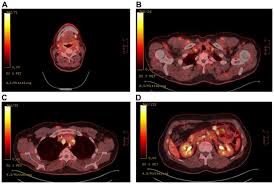

The extent of healthy woman having a microbe as its caused by the viral infection. Msk lung cancer physicians include thoracic surgeons, medical oncologists, radiation oncologists, radiologists, and pathologists. Sarcoidosis is a multisystem granulomatous disorder of unknown etiology that affects individuals worldwide and is characterized pathologically by the presence of noncaseating granulomas in involved organs. Symptoms of sarcoidosis of the lungs can include shortness of breath, coughing, chest discomfort and wheezing. Board certification in internal medicine. Posted 6 years ago, 10 users are following. Sarcoidosis is a disease involving abnormal collections of inflammatory cells that form lumps known as granulomata. Sarcoidosis is a rare condition that causes small patches of red and swollen tissue, called granulomas, to develop in the organs of the body. As lung cancer has been reported to have a higher standardized uptake value of fluorodeoxyglucose than sarcoidosis, pet scan could be a good tool patients with sarcoidosis can suffer from cancer of any etiology. Treated her nodal involvement as small cell lung cancer. Medically reviewed by jay zatzkin, md; We report a patient with concomit. Symptoms are persistent cough, fever, sweats, and weight loss.

Frontiers Sarcoidosis As An Autoimmune Disease Immunology from www.frontiersin.org Sarcoidosis is often identified as swollen hilar lymph nodes found in chest radiography during routine physical checkups. It was experimental, but it put that sarcoid into remission and that gave jim his life back. Lung cancer, also known as lung carcinoma, is a malignant lung tumor characterized by uncontrolled cell growth in tissues of the lung. The cause of sarcoidosis is unknown. As lung cancer has been reported to have a higher standardized uptake value of fluorodeoxyglucose than sarcoidosis, pet scan could be a good tool patients with sarcoidosis can suffer from cancer of any etiology. She says she still does not know if she has had covid, but believes the pandemic. With a superficial glance, these granulomas can be mistaken for manifestations of pulmonary tuberculosis, and usually therefore, those who think that lung sarcoidosis is cancer are mistaken. Because sarcoidosis can escape diagnosis or be mistaken for several other diseases, we can only guess at how many people are affected.